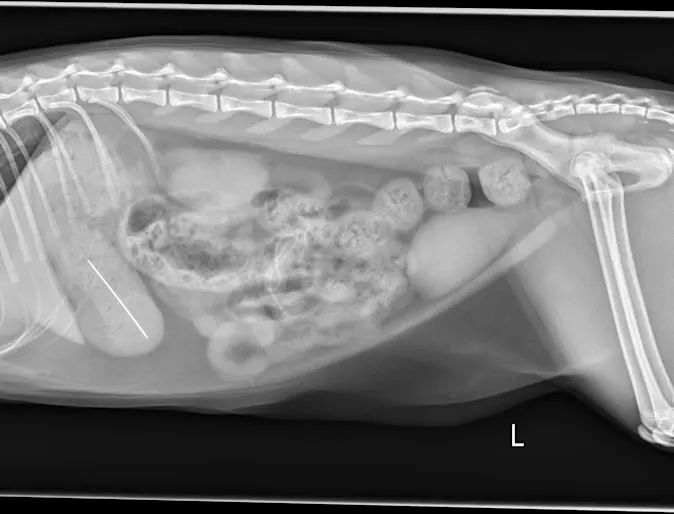

September 2023: Charlie Brown

Case Study

Good Grief! Charlie Brown presented to Mountainside Animal Emergency & Specialty when his owners noticed that he had ongoing vomiting and a decreased appetite.